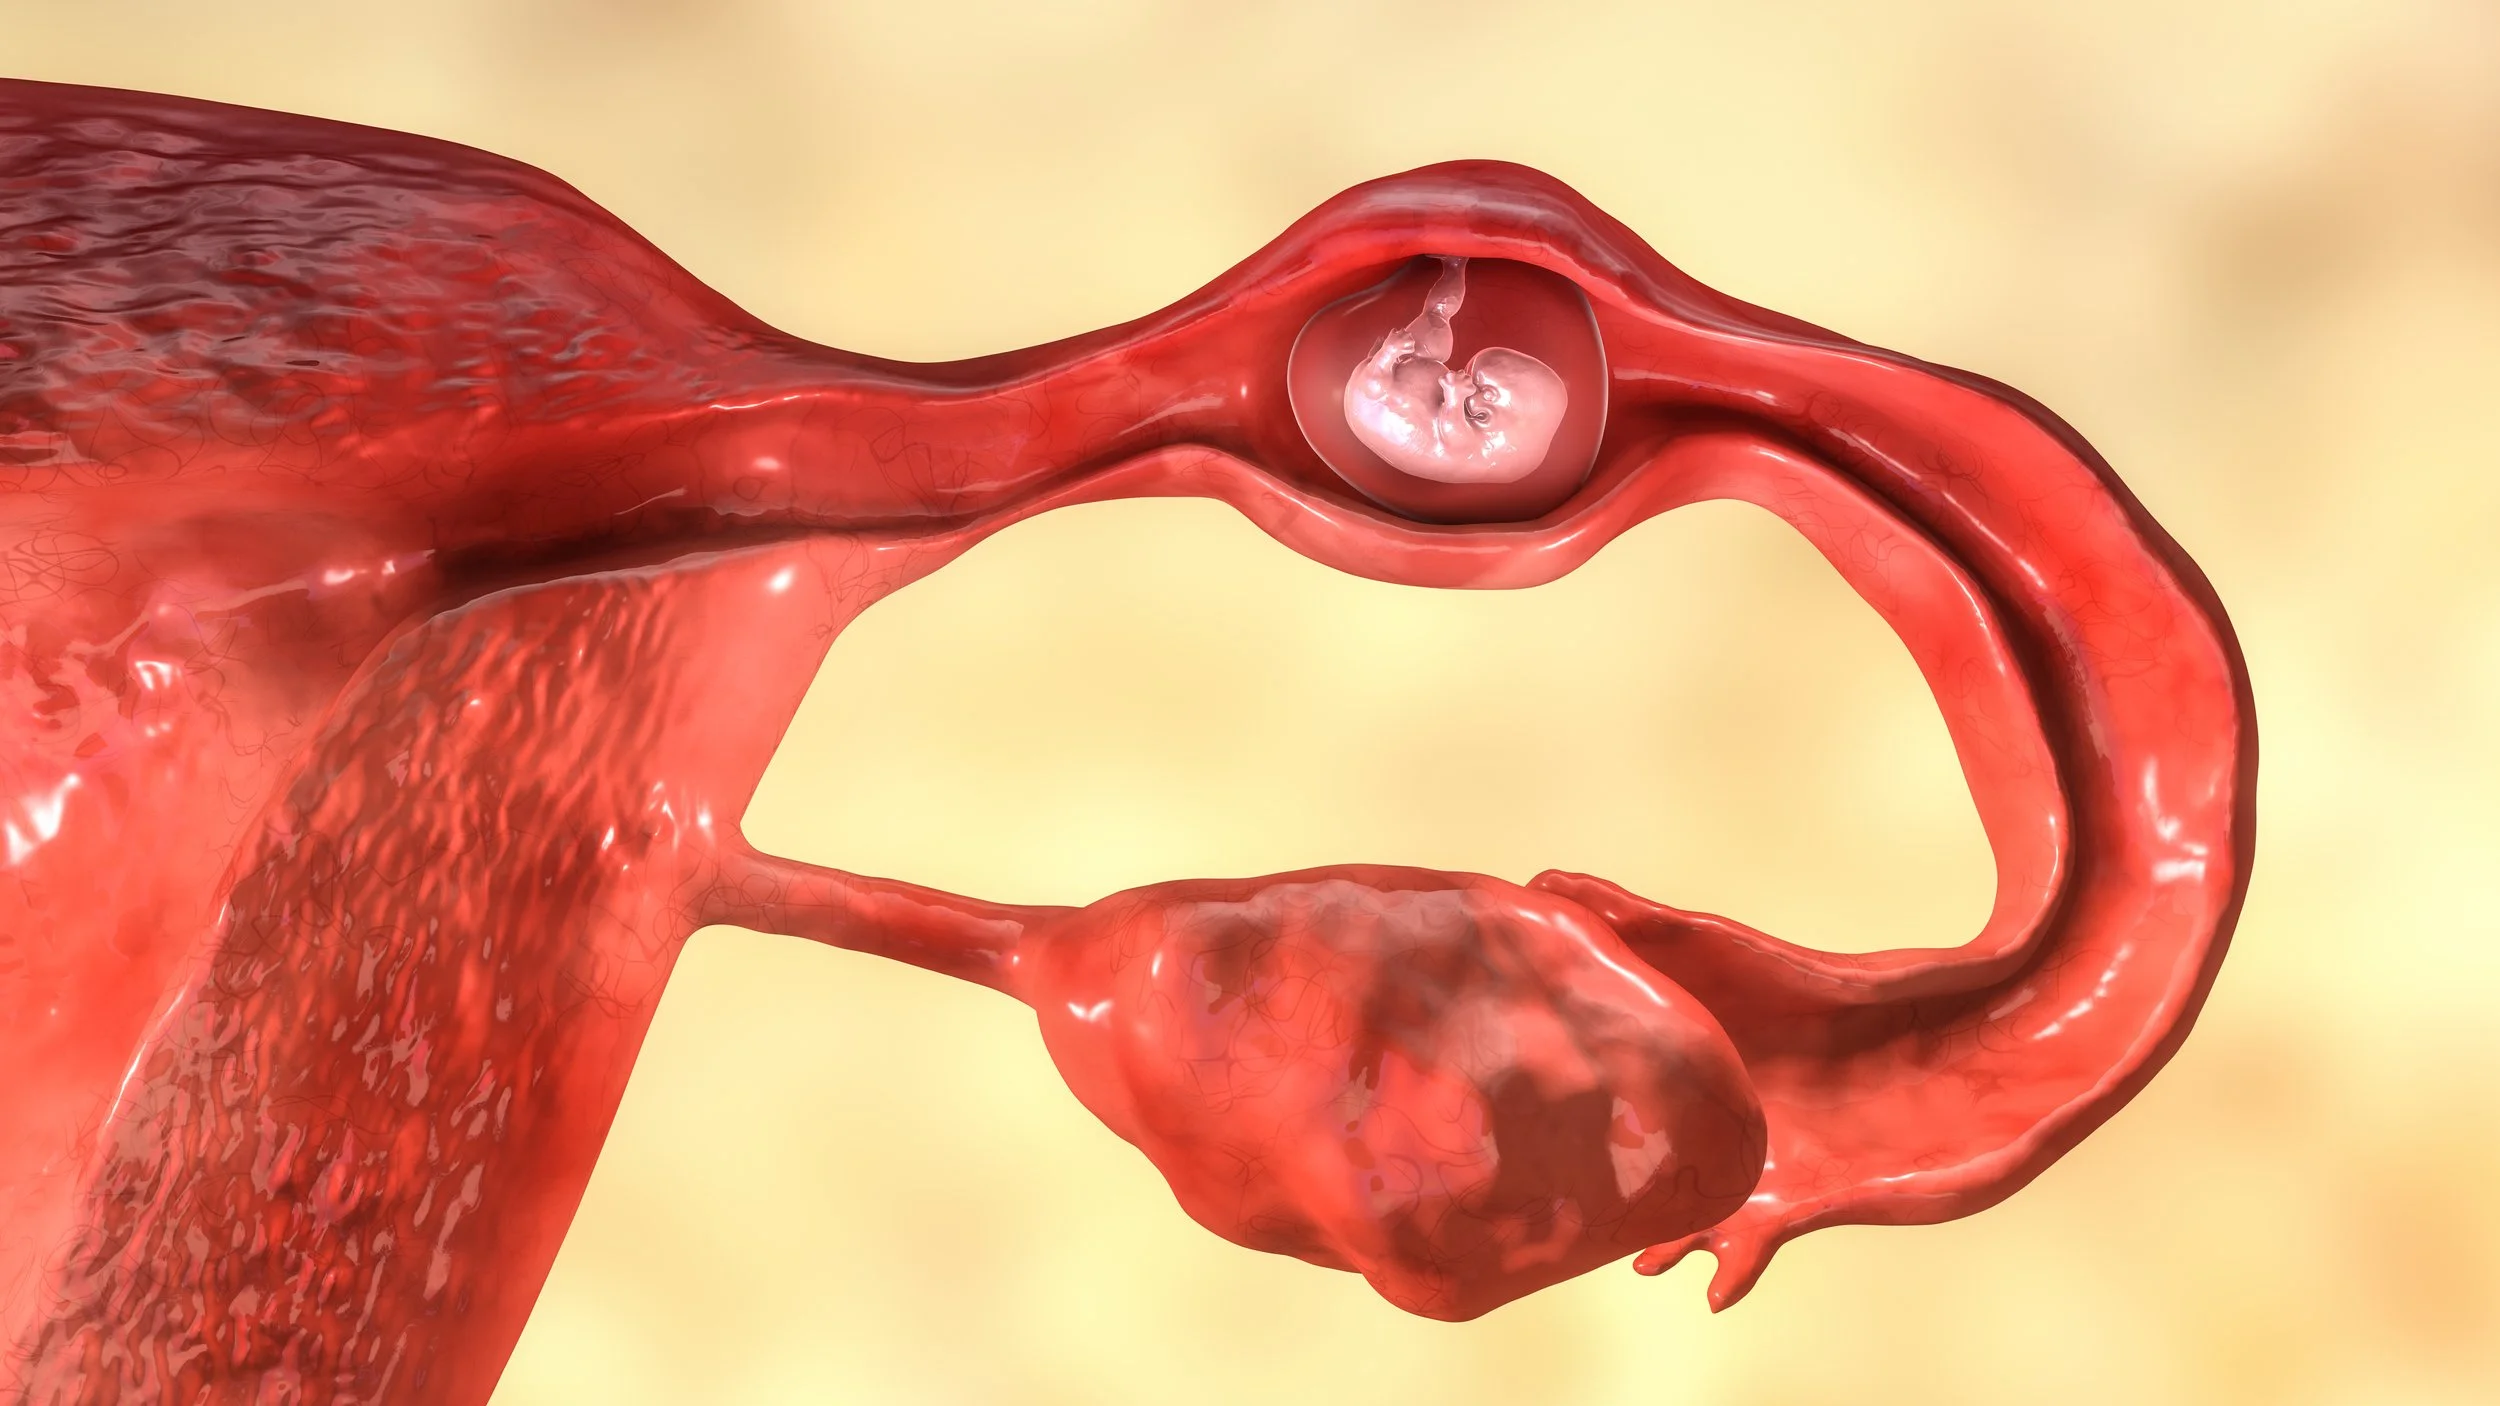

The Beta-HCG and Ectopic Pregnancy. Myth-Busting.

OBGYN Dillon Warr OBGYN Dillon Warr

You can’t rule out an ectopic pregnancy with a low or “reassuring” β-hCG. The discriminatory zone only applies to normal intrauterine pregnancies, not ectopics—and many ruptures occur with levels well below 1,500 mIU/mL. Every symptomatic pregnant patient needs an ultrasound, regardless of hCG value. No hCG cutoff, and no pattern of symptoms, safely excludes an ectopic.